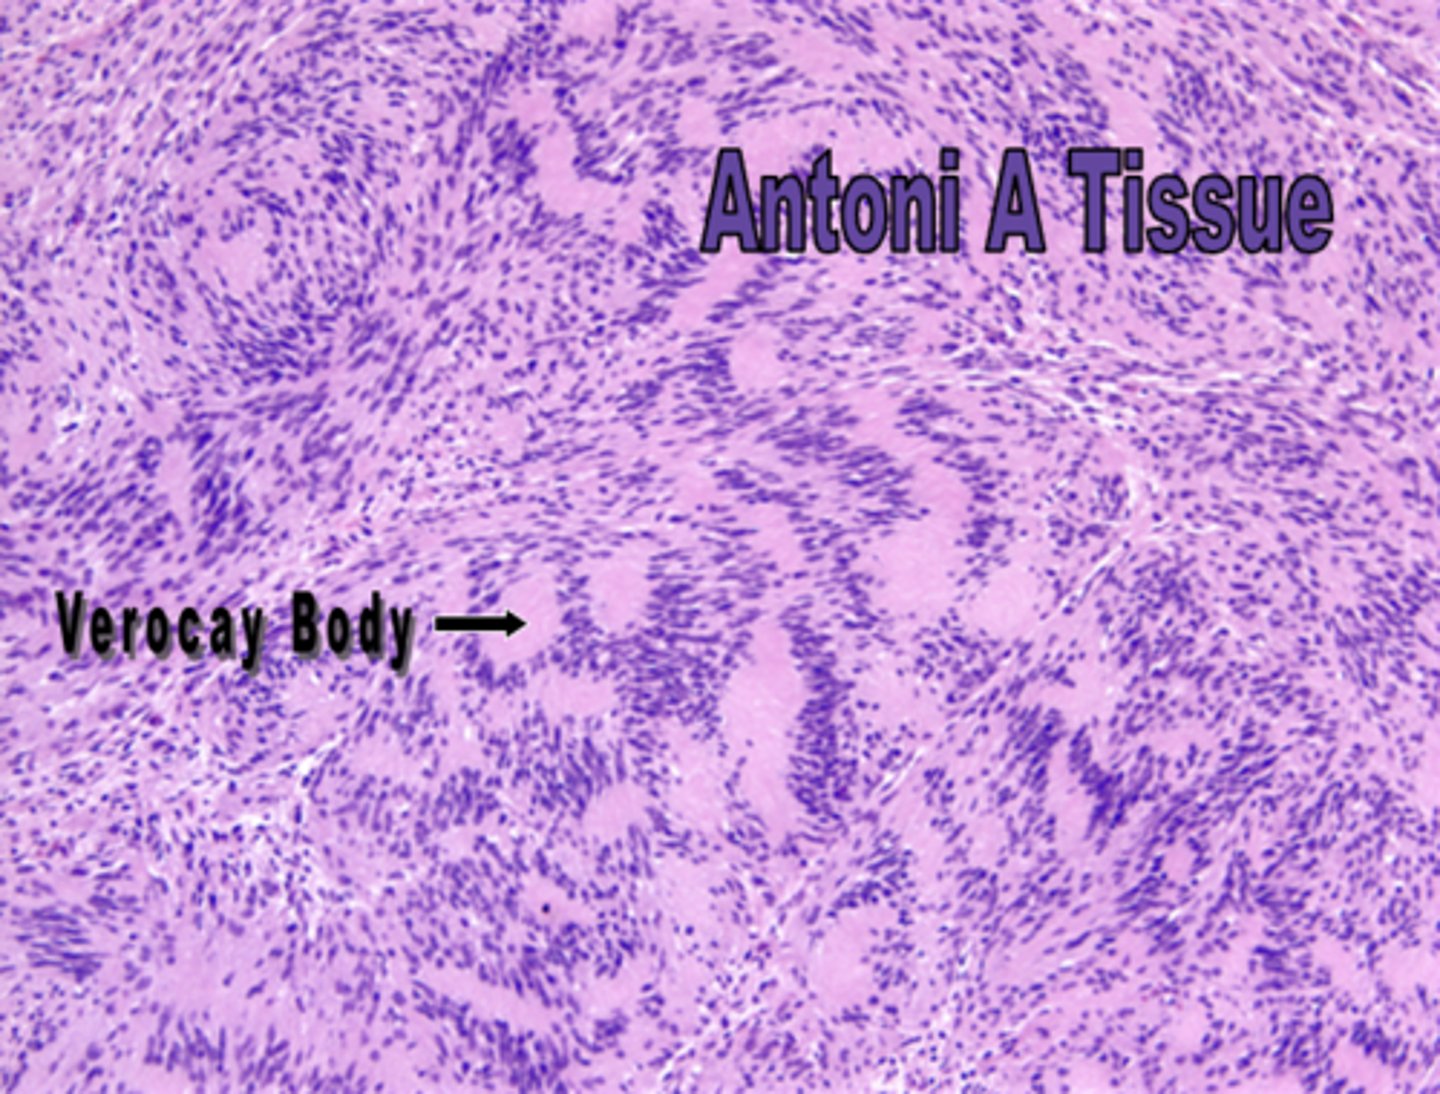

what is neurilemmoma?

benign tumor of Schwann cell origin that is a smooth surfaced, pink nodule

Verocay bodies are indicative of what lesion?

neurilemmoma

is there a better prognosis for neurofibroma or neurilemmoma?

neurilemmoma